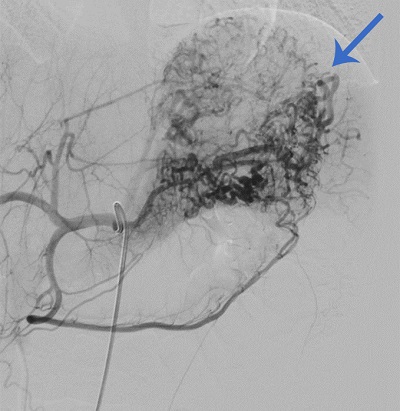

En el episodio actual, acudió a Urgencias por un episodio de hematemesis, melenas y síncope que precisó en dos ocasiones la administración de suero salino fisiológico 0,9% a 20 ml/kg e ingreso en UCIP para vigilancia. Presentó una anemización progresiva hasta hemoglobina de 6,9 g/dl, precisando transfusión de dos concentrados de hematíes. Durante su ingreso se realizó ecografía abdominal y gastroscopia sin alteraciones significativas y valoración por Otorrinolaringología descartando foco del sangrado a dicho nivel. Al tercer día de ingreso, se realizó angiografía mostrando una malformación vascular de tipo arterial en región fúndico-cardial en aspecto de “ovillo”.

Ante dichos hallazgos se decidió traslado a nuestro centro, donde se realizó una arteriografía diagnóstico-terapéutica. La embolización de la malformación transcurrió sin incidencias (Figs. 1 y 2).

| Figura 1. Malformación arterial gastropancreática con aspecto de ovillo. Irrigación principal a expensas de arteria gástrica izquierda y arteria esplénica. El componente gástrico se comporta como una lesión de Dieulafoy |